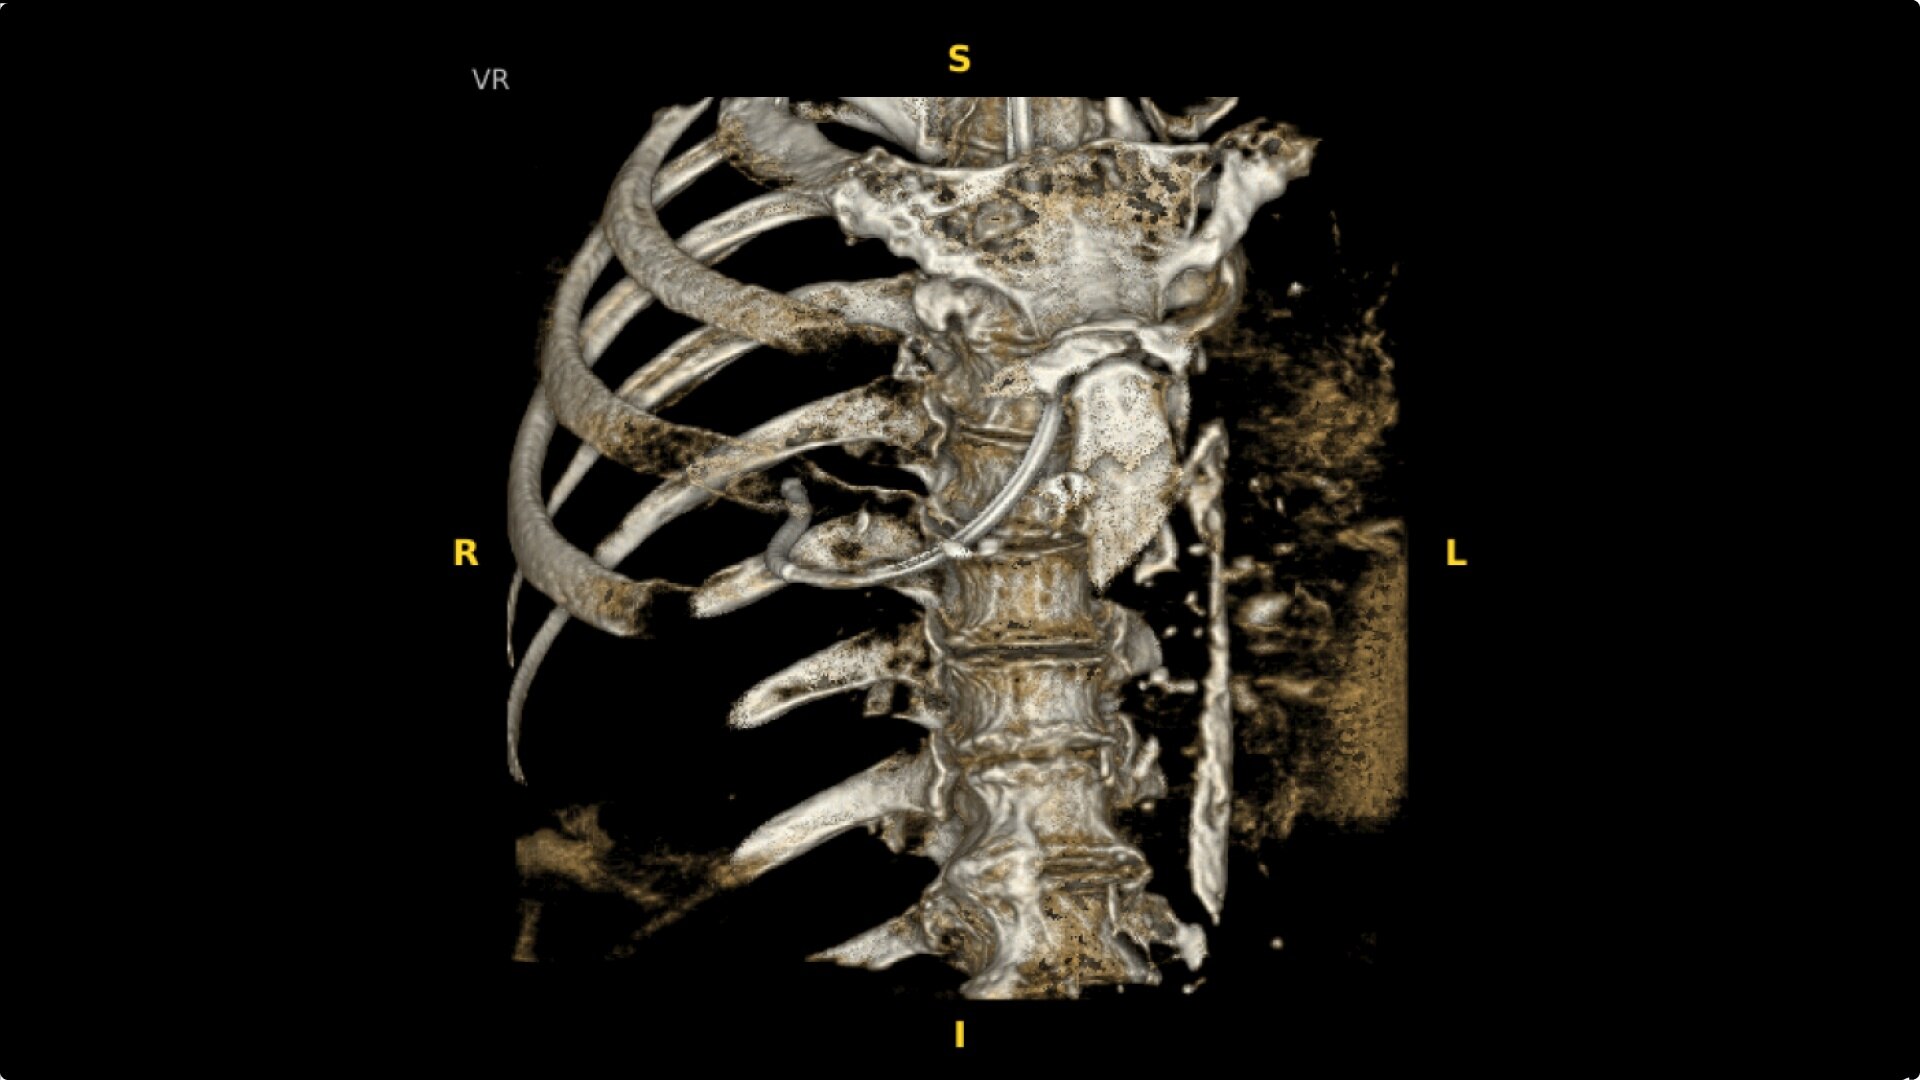

The OEC 3D provides comprehensive imaging with precise 19 cm x 19 cm x 19 cm 3D volumes and exceptional 2D images intraoperatively.

The OEC 3D presents five perspectives: Axial, Coronal, Sagittal, MIP, and VR, on a 4K display for clear and detailed review of 3D volumes and 2D images.